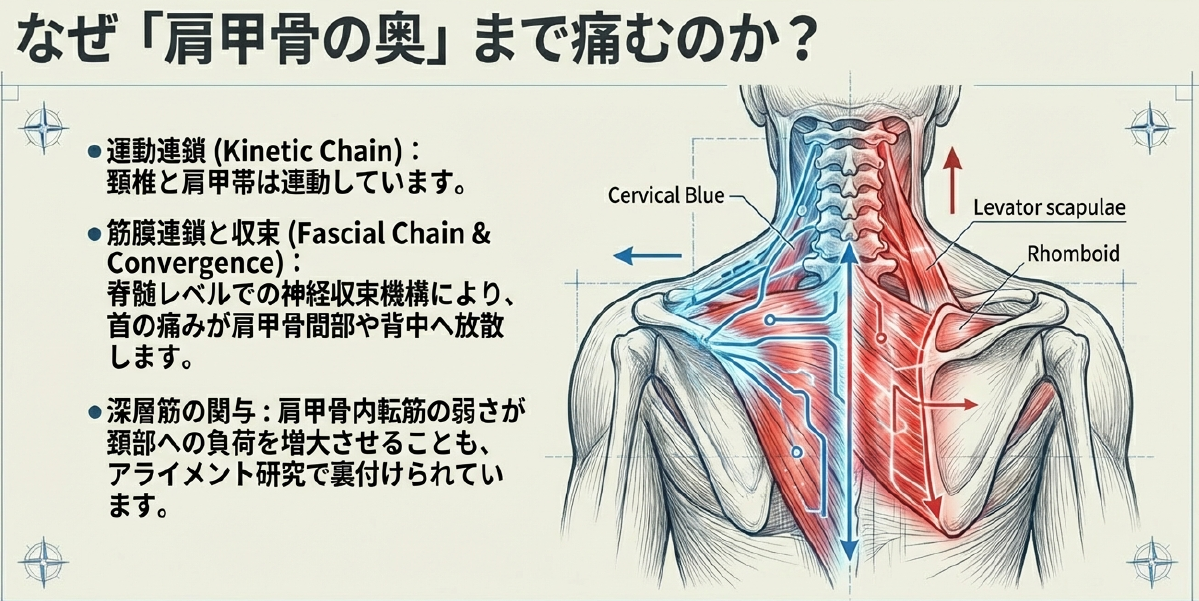

近年の中枢痛み研究では、こうした急性入力が一時的にノチセプターを過敏化し、痛みの拡大を招くことが示唆されています。患者さんが「首を動かすと肩甲骨の奥まで響く」と訴えるのは、筋膜連鎖や脊髄レベルの収束機構によるもので、局所治療だけでは不十分な理由もここにあります。

ただし、全てが筋由来とは限りません。頚椎の退行性変化がある場合、椎間板の水分喪失や骨棘が基盤となり、急性負荷で椎間関節包が刺激されて炎症様疼痛を誘発します。高齢者や長年の不良姿勢習慣がある人では、このパターンが潜伏しやすく、「いつもの寝違えのはずが長引く」ケースに発展します。炎症主体なら安静時痛や熱感が加わり、神経根圧迫の兆候として手への放散痛も見られます。こうした鑑別は、触診に加え可動域テストや神経学的検査で可能ですが、画像診断は急性期では過剰です。むしろ、機能的アセスメントで肩甲骨の挙上・後退パターンを確認すると、深層筋の関与が明らかになります。例えば、肩甲骨内転筋の弱さが頚部負荷を増大させるという知見は、肩甲骨アライメント研究から裏付けられています。